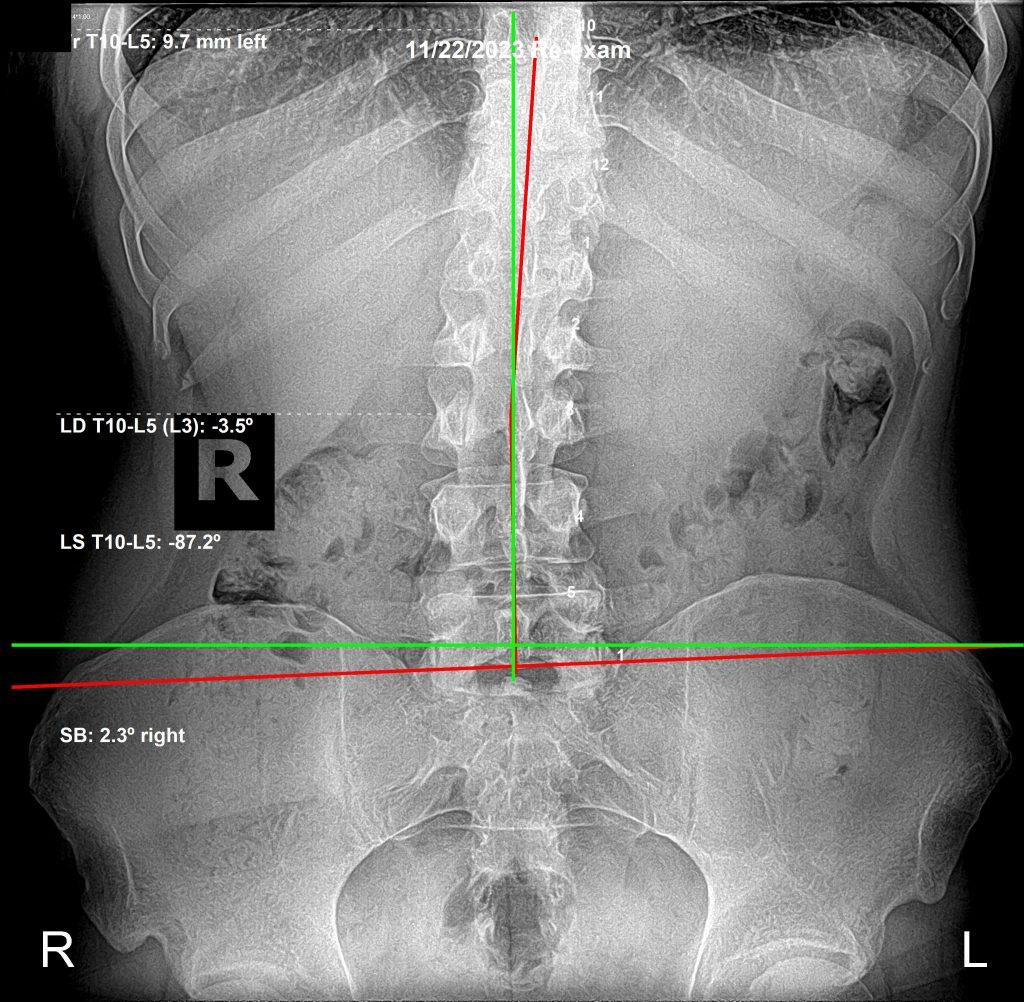

AP lumbar X-ray after chiropractic care

AP View — After Care

All of these new issues are related. We are kinetic chains — everything connected through motion. As his spine changed, specifically his pelvis, other areas appeared worse on film — even though functionally he was improving.